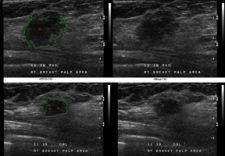

B-CAD 2.2 for breast ultrasound imaging is available in two formats: as a software product intended for Medipattern’s resellers to load onto workstations and as a plug-in module for the Sectra IDS5 workstation. B-CAD 2.2 electronically analyzes breast masses using all of the American College of Radiology’s BI-RADS (Breast Imaging Reporting and Data System) feature categories: size, shape, orientation, margin, lesion boundary, echo pattern, post-acoustic features and calcification in masses. Version 2.2 reportedly gathers all of the information required to track multiple lesions and completes the imaging procedure by automatically documenting the results in a pre-formatted report.